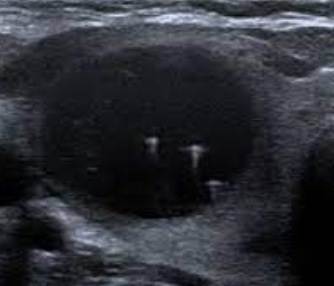

Q

Thyroid ultrasound

A

Colloid nodule

Note: Comet tail artifact.